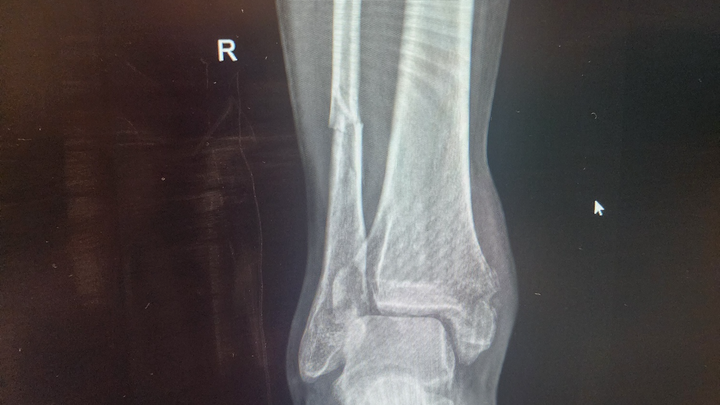

I’m reaching out during a really challenging time. I recently suffered a fractured ankle that requires orthopedic surgery. While I’m fortunate to have insurance, the out-of-pocket expenses for the surgery, follow-up care, and recovery are still significant.